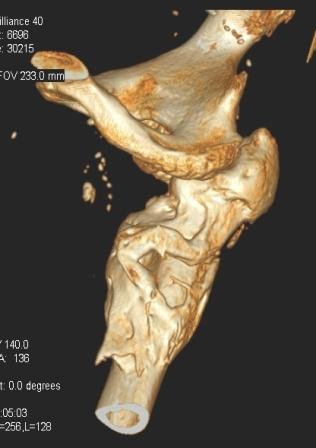

[Ortho] Сросшийся со смещением чрез-подвертельный перелом

----------- следущая часть -----------

Вложение не в текстовом формате было извлечено…

Имя     : уменьш (8).jpg

Тип     : image/jpeg

Размер  : 22233 байтов

Url     : http://weborto.net:8080/pipermail/ortho/attachments/20091031/f055a08c/attachment-0008.jpg